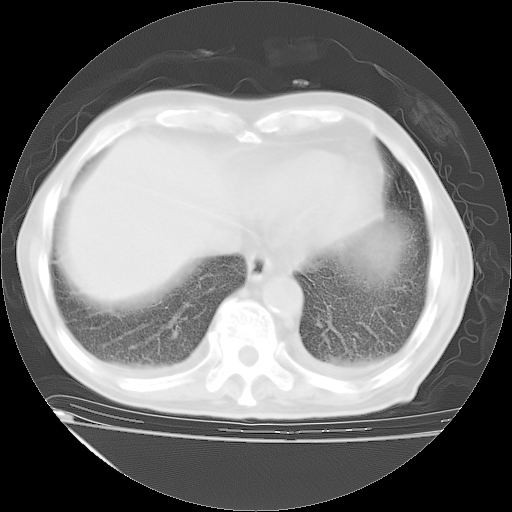

补充下:5月9日胸部CT:似乎已见双下肺胸腔积液了,鉴于目前有下肢水肿,肝功示:白蛋白低,应注意多浆膜腔积液(漏出液可能大?),需注意!

甲强龙80mg/日+抗结核治疗(异烟肼+利福霉素+乙胺丁醇)10天。复查肺部CT。

治疗10天肺部CT